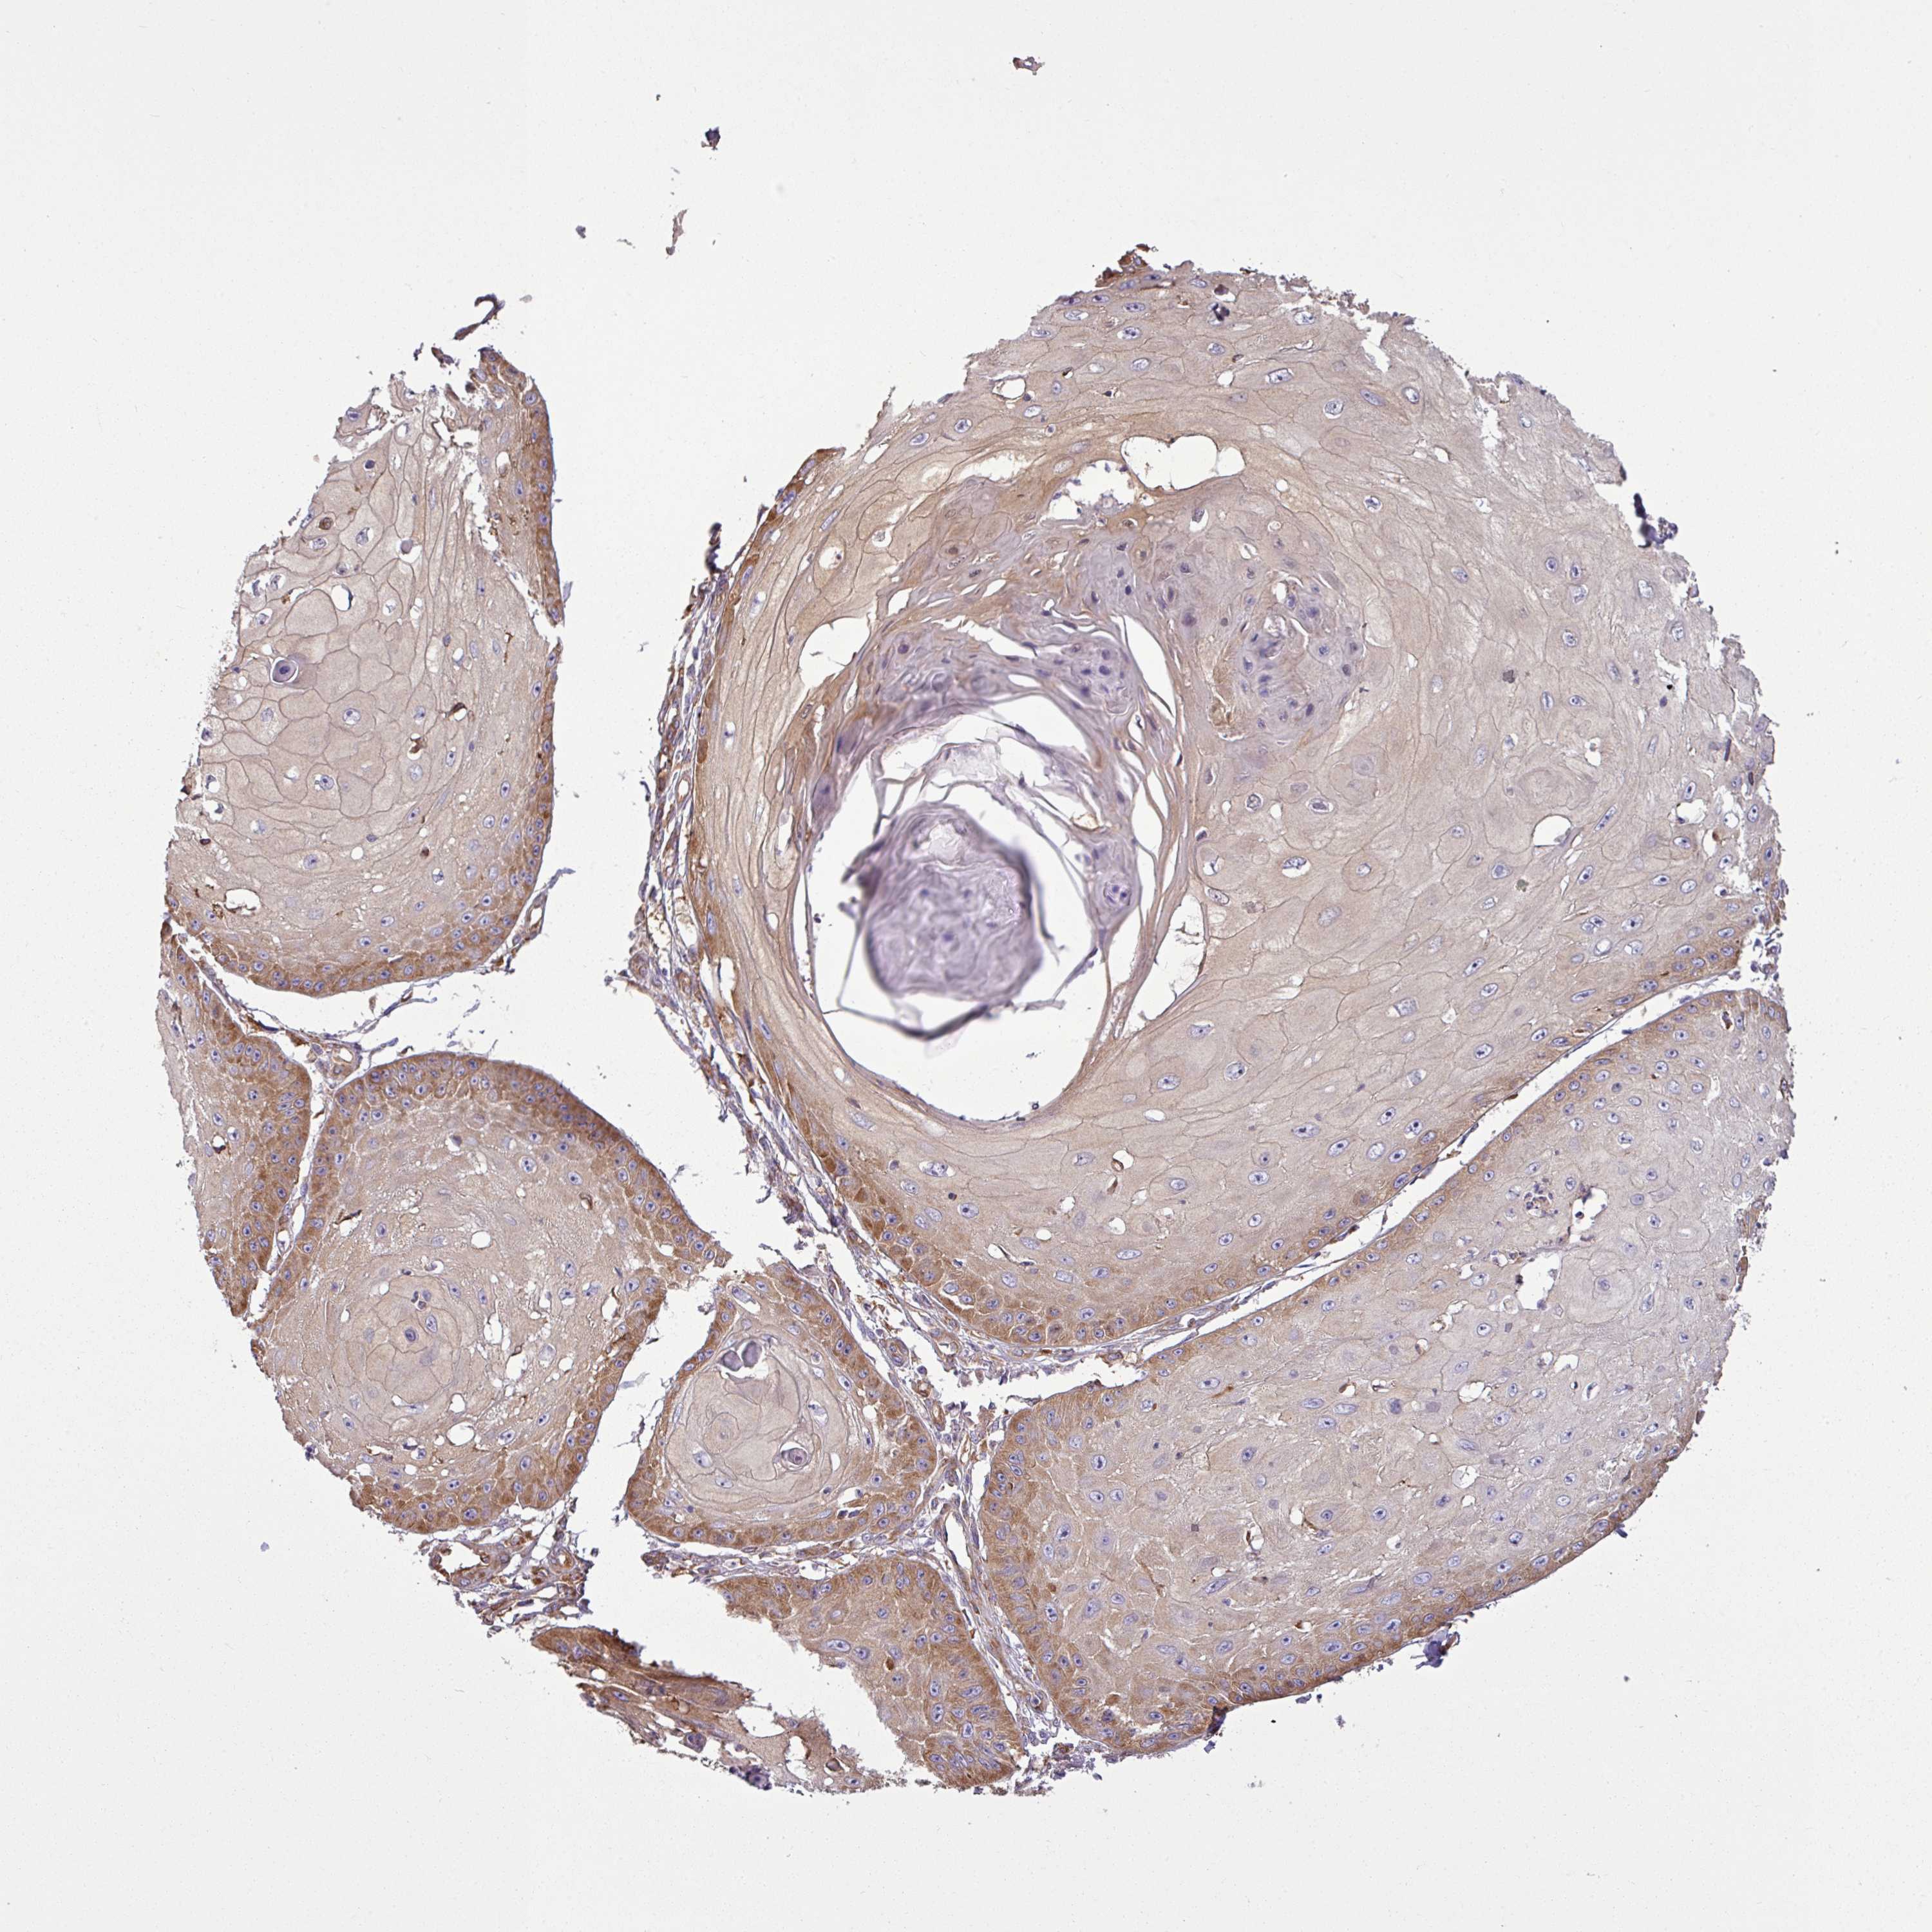

Basal cell and squamous cell cancer

SKIN CANCER - Protein expressioni

A mouse-over function shows sample information and annotation data. Click on an image to view it in a full screen mode. Samples can be filtered based on level of antibody staining by selecting one or several of the following categories: high, medium, low and not detected. The assay and annotation is described here.

Antibody stainingi

Antibody staining in the annotated cell types in the current human tissue is reported as not detected, low, medium, or high, based on conventional immunohistochemistry profiling in selected tissues. This score is based on the combination of the staining intensity and fraction of stained cells.

Each image is clickable and will lead to virtual microscopy that enables deeper exploration of all samples and also displays staining intensity scores, fraction scores and subcellular localization as well as patient and tissue information for each sample.

Antibody HPA049854

Antibody HPA056520

Staining

High

Medium

Low

Not detected

Intensity

Strong

Moderate

Weak

Negative

Quantity

>75%

75%-25%

<25%

None

Location

Nuclear

Cytoplasmic/membranous

Cytoplasmic/membranous,nuclear

Basal cell carcinoma

Squamous cell carcinoma, NOS

Squamous cell carcinoma, metastatic, NOS